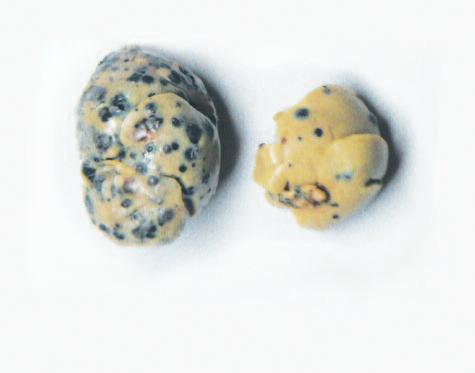

Per l'esperimento successivo abbiamo suddiviso gli animali non in grado di produrre la propria vitamina C in due gruppi. Poi agli animali di entrambi i gruppi è stato inoculato il cancro della pelle (melanoma). In seguito, un gruppo è stato sottoposto ad una dieta contenente una quantità ottimale di vitamina C, mentre l'altro gruppo ha ricevuto una dieta carente di questo nutriente essenziale.

Nella pagina a fianco sono riportati gli incredibili risultati documentati per la prima volta in questo esperimento. Gli animali con carenza di vitamina C nella dieta sviluppano tumori di grandi dimensioni, che crescono sempre più diffusamente nei tessuti limitrofi (figura A). Al contrario, gli animali con una dieta ricca di vitamina C hanno sviluppato meno tumori e tumori più piccoli. Cosa ancor più importante, in questo gruppo un quantitativo ottimale di vitamina C nella dieta ha portato alla formazione di tessuto connettivo di confinamento (incapsulamenti) dei tumori (figura B). Questo esperimento dimostra che la presenza o l’assenza di vitamina C è un fattore decisivo per stimolare la difesa del corpo contro i danni del cancro.

AA. Un tumore cancerogeno sviluppato in un topo, non in grado di produrre vitamina C che viene sottoposto ad una dieta carente di vitamina C.

Notare che il confine diffuso del tumore (freccia) con le cellule tumorali che facilmente invade i tessuti circostanti

BB Con l’integrazione di vitamina C, i topi dello stesso esperimento hanno eretto una forte barriera di tessuto connettivo attorno al tumore, confinandolo alla posizione originale E' evidente da questa immagine che è improbabile che i tumori incapsulati invadano il tessuto circostante e creino una metastasi.